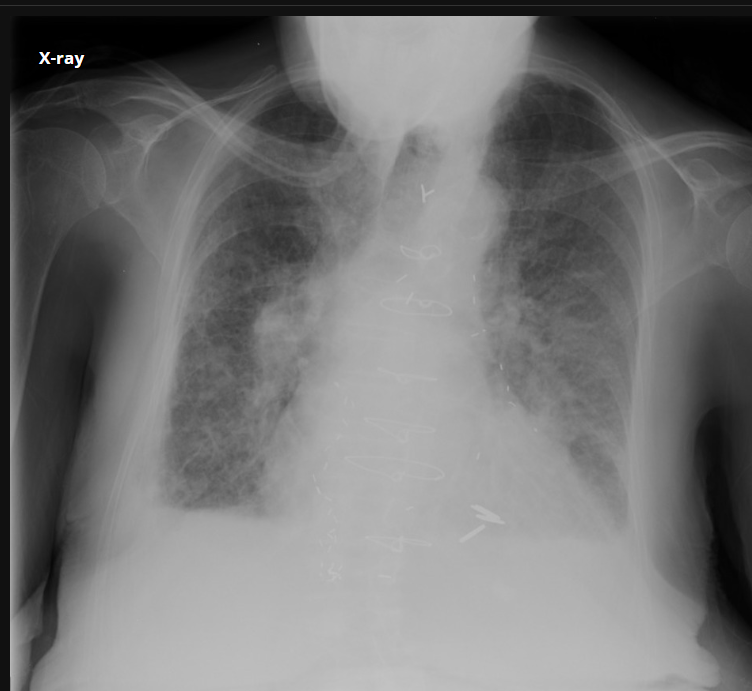

COVID-19 Pneumonia.